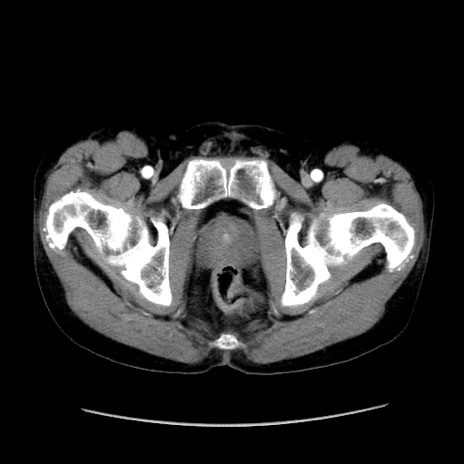

症例37(横断像)

【症例】40歳代 男性

【主訴】腹痛

【現病歴】4時間ほど前に電車に乗車中に臍部上より腹痛出現。徐々に増悪し起立困難となり、救急外来受診。生ものは数日食べていない。今朝お雑煮を食べた。

【身体所見】BT 36.8℃、BP 117/84mmHg、HR 91/min、SpO2 97%、苦悶様、腹部:臍上部広範囲圧痛あり、反跳痛±

【データ】WBC 8100、CRP 0.03